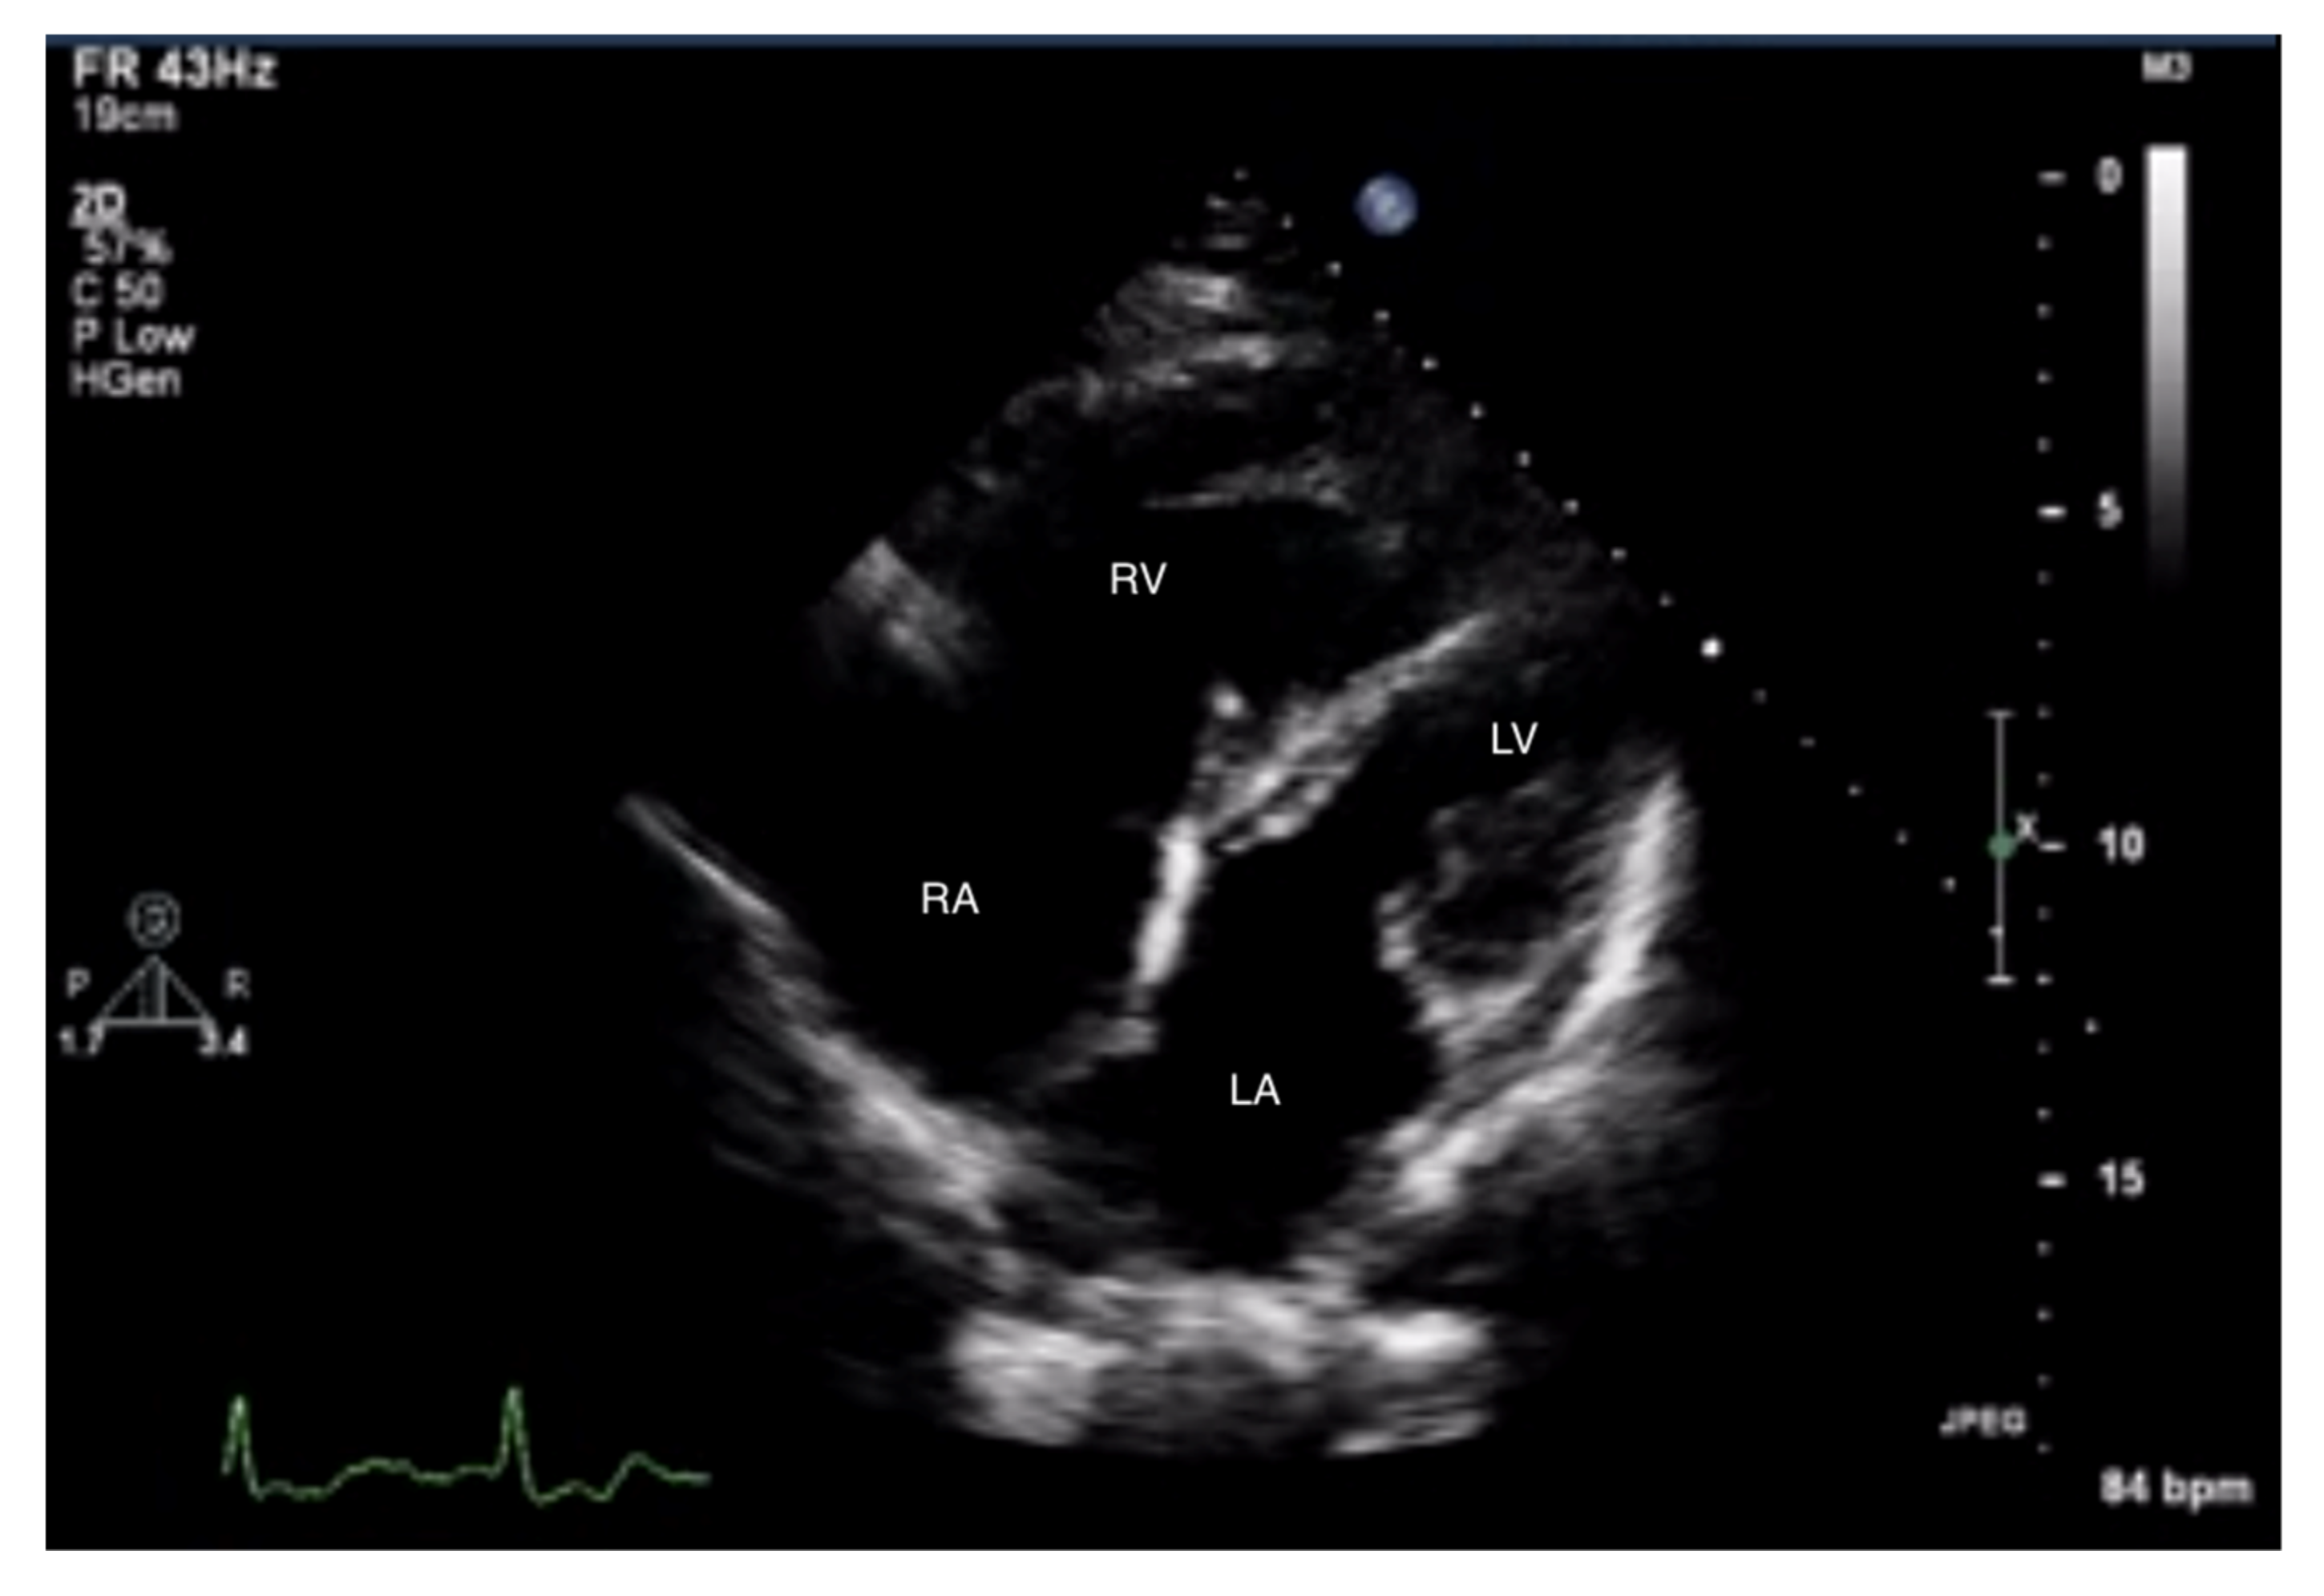

Figure 3.

Enlarged right ventricle and right atrium. An abnormal size ratio between the right and left heart. 2D-TTE, 4CH view. 2D-TTE: two-dimensional transthoracic echocardiography; 4CH: four-chamber.